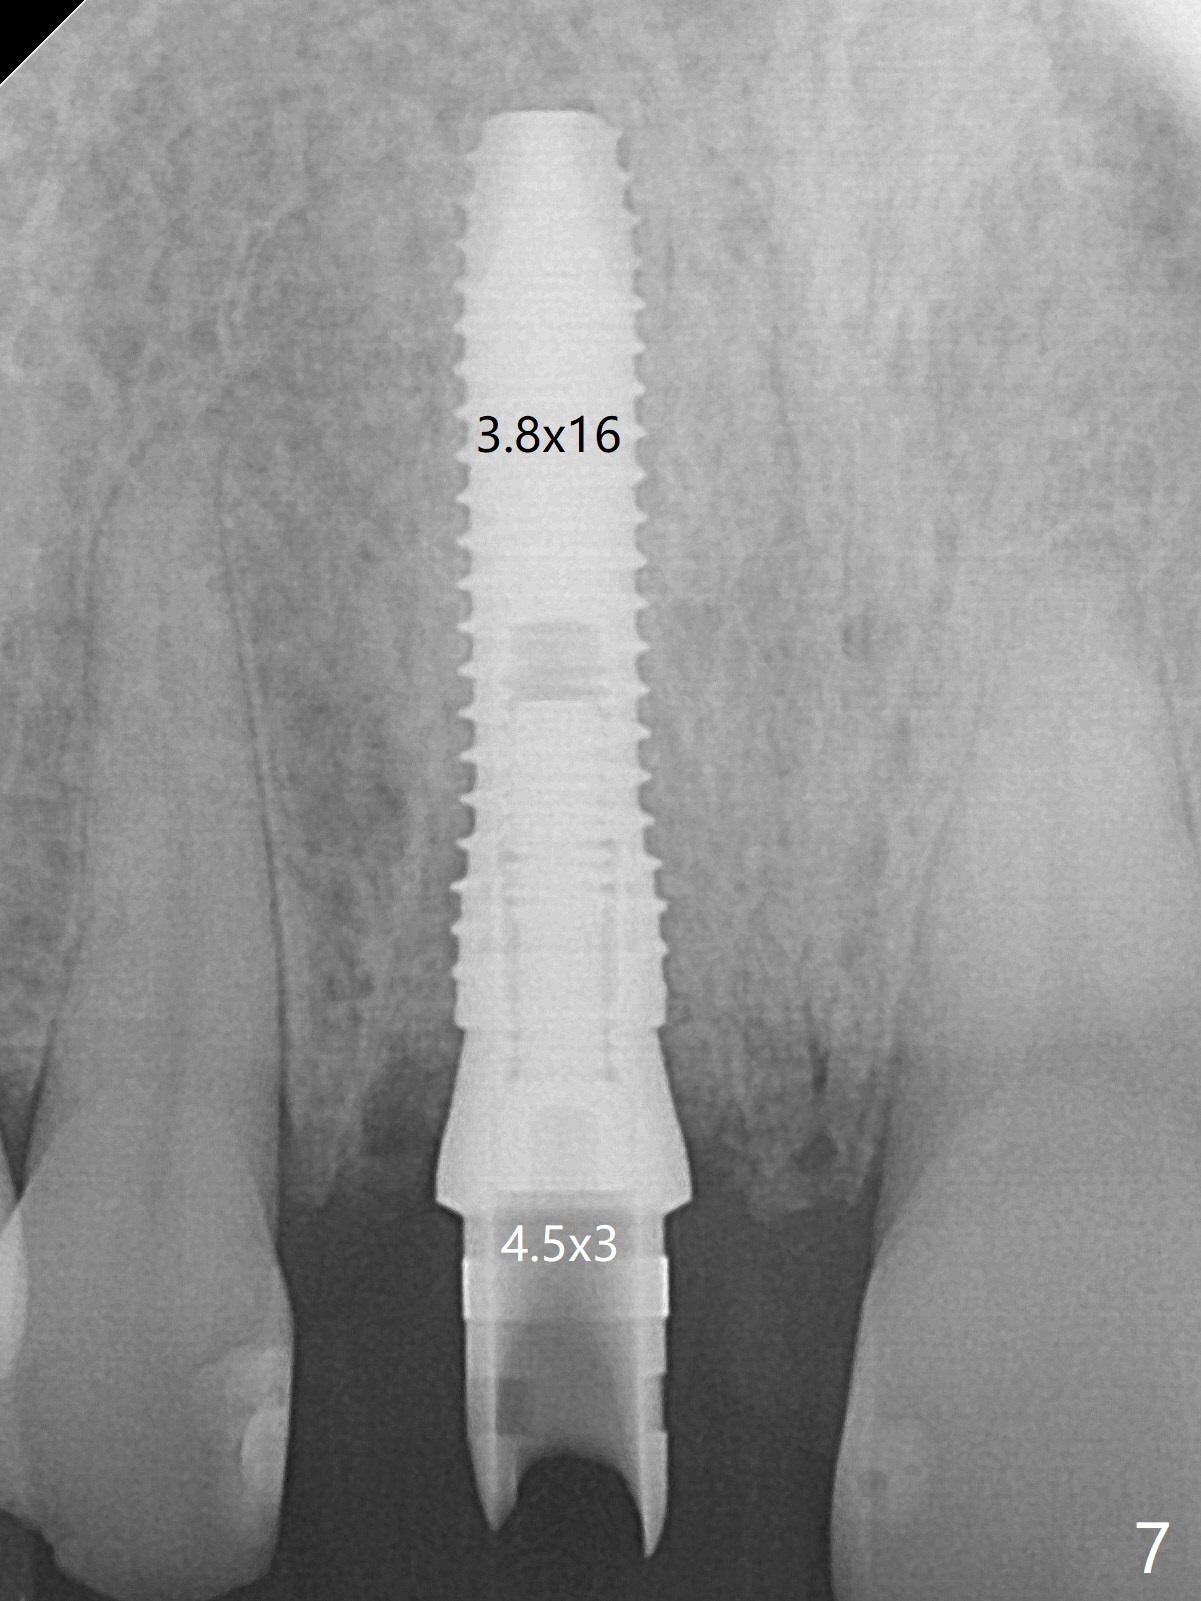

The buccal gingiva at #8 is erythematous (Fig.1: *), which is associated with the tooth fracture line (Fig.2 with granulation tissue: *). The buccal plate remains intact. Osteotomy is initiated in the palatal wall of the socket (Fig.3,4). The initial osteotomy depth is 16 mm (Fig.5); the trajectory is going to be adjusted as shown by arrows. The trajectory improves when a 3.8x15 mm dummy implant is placed (Fig.6). The definitive implant (3.8x16 mm) appears to be placed at an appropriate level (Fig.7). A 4.5x3 mm temporary abutment is inserted for an immediate provisional. As routine, Vera Graft is placed in the buccal gap. The buccal gingival erythema reduces without tenderness 1 week postop (Fig.8). Although the provisional is unstable, there is no bone loss 2 months 20 days postop (Fig.9). Because of the loose provisional (partial detachment from the underlying temporary abutment), impression is taken earlier (3 months postop, Fig.10,11). Due to the pointed abutment tip, the crown is redone 3 times. By the time of cementation (nearly 5 months postop), the socket appears to have healed (Fig.12).